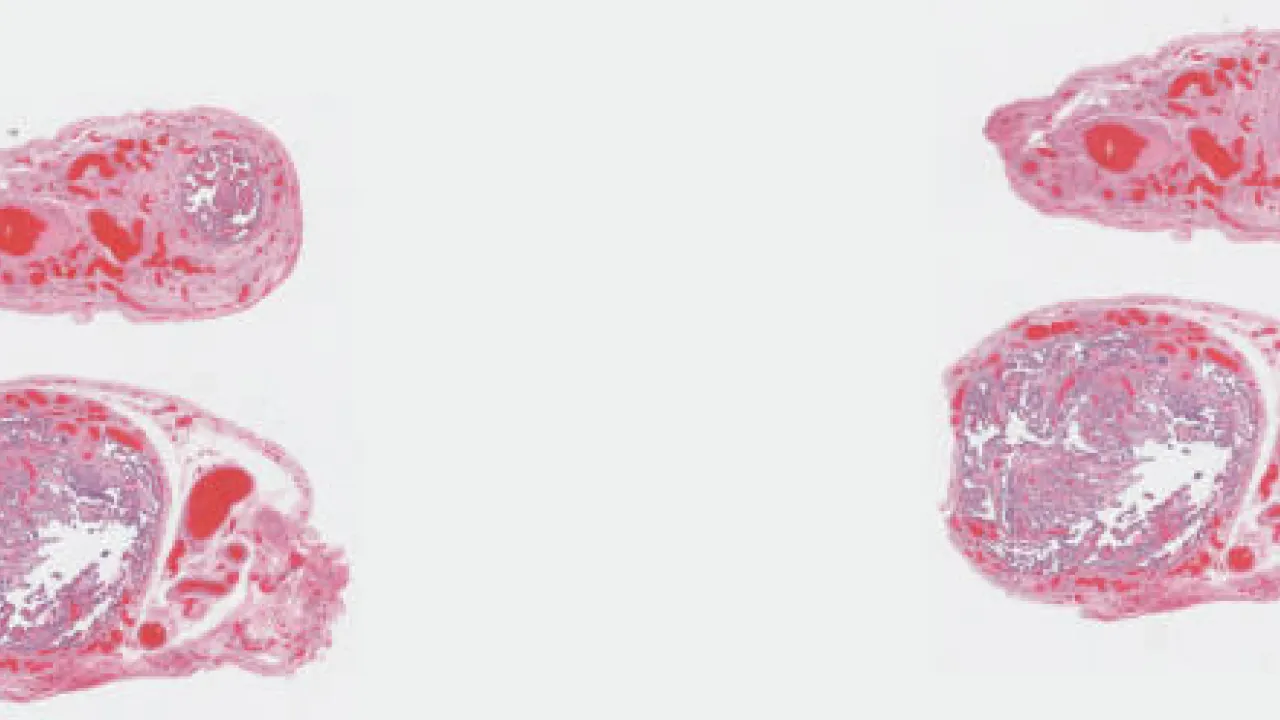

Fallopian tube, metastatic carcinoma